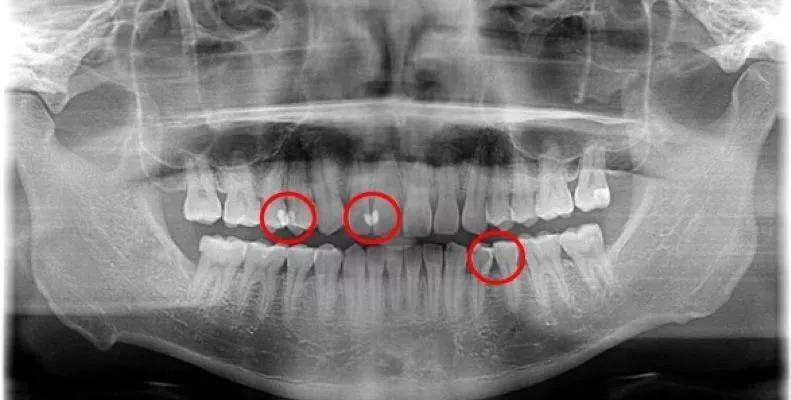

很多早期邻面龋不能被发现和及时治疗,因为本病早期的表现有牙釉质的脱矿,表面观察不到,拍X线片上变化也不大。

随着邻面龋的进一步发展,肉眼观察牙齿邻面颜色暗黑,对光线的透射性减弱。X线显示牙齿邻面出现三角形低密度阴影。牙齿遇冷热酸甜等刺激产生酸痛,经常出现大量食物残渣嵌塞,伴有腐臭味。龋损进一步扩展时,会发生颌面牙体组织的折裂。